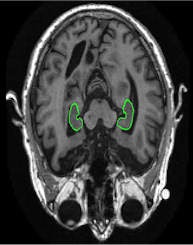

PredictAD aims to extract biomarkers from heterogeneous patient data and integrate them for objective and evidence-based diagnostics. For example its reasearch team is exploring how MRI can be used to measure atrophy in the mediotemporal lobe, which is recognized as a hallmark of Alzheimer's.

In current clinical practice, images are interpreted mostly only by visual inspection, but there is a need for objective measurements, according to Dr. Jyrki Lötjönen, the scientific coordinator of the project and principal scientist and adjunct professor of signal and image processing at the VTT Technical Research Centre in Tampere, Finland.

To meet this need, the PredictAD team has developed tools for measuring the size of the hippocampus, the atrophy rate of the hippocampus, and two approaches based on comparing patient data with previously diagnosed cases available in large databases. PET is also being studied in the project. A novel tracer developed recently especially for diagnostics of Alzheimer's disease provides promises for very early diagnosis of the disease.